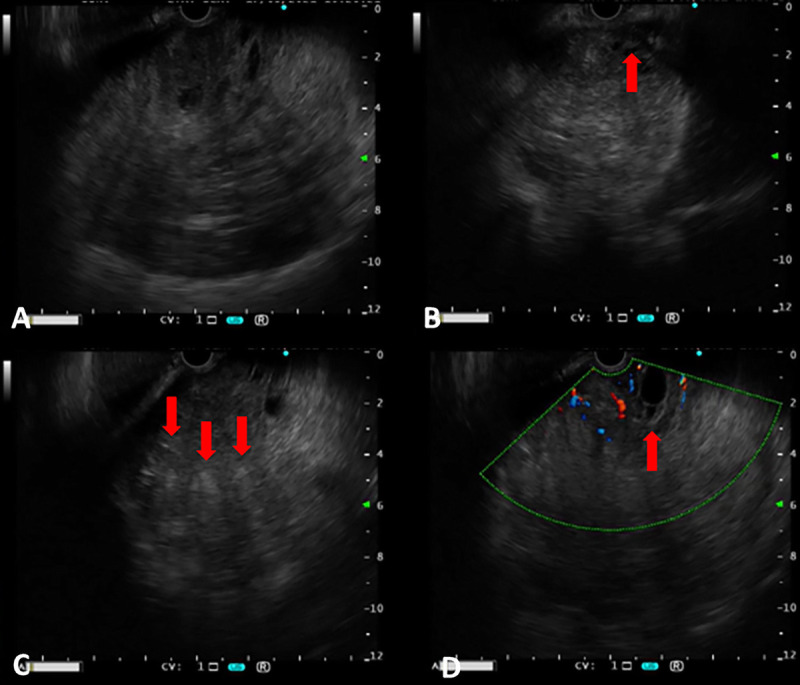

Succinate dehydrogenase-deficient gastrointestinal stromal tumor of the stomach: EUS and contrast-enhanced EUS features (with videos).